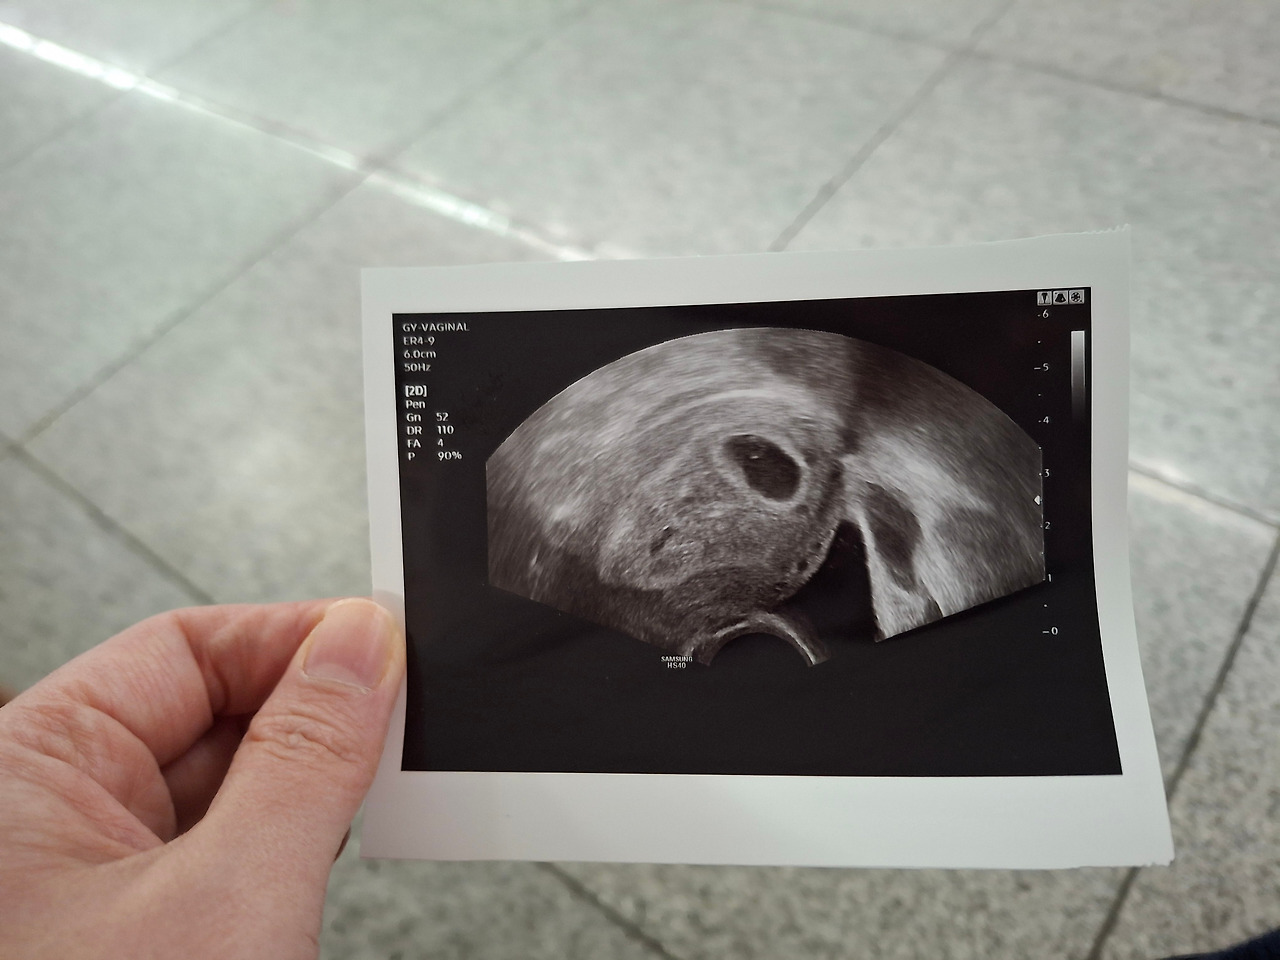

임신 7주 차, 135bpm으로 정상 범위의 아기의 심장 소리를 처음 들었을 때

우리는 비로소 안도의 숨을 내쉬었다.

20260309_084953.jpg

심장 소리를 들으면 유산 확률이 많이 낮아진다고 했다.